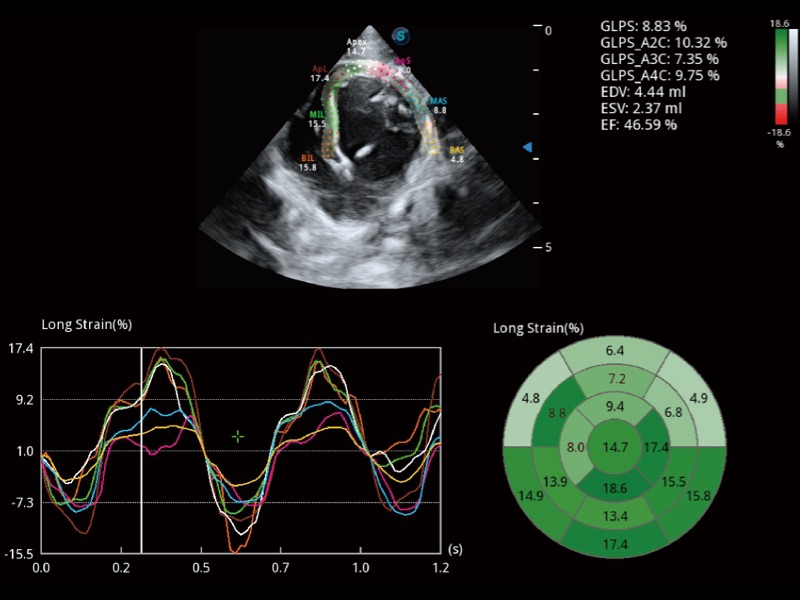

能够基于左心室壁追踪和辛普森法,自动计算射血分数,支持多个可移动点描迹,与手动测量相比,极大节省了动物医生的时间和精力。

具备多种协议可选,同时支持17阶段划分法和专业的SE报告。

通过360度任意调节3条M型取样线,在同一心动周期上观察心脏不同位置的运动曲线,得到准确的心功能测量数据,有效评估心肌运动及左心室功能。

实时用颜色表示心肌组织运动,观察和定量组织的运动情况,对快速检测与评估心肌的灌注和活性、电传导及心肌收缩和舒张功能等均能提供重要的诊断信息。